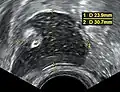

Large ovarian cyst Dermoid cyst in vaginal ultrasonography

Dermoid cyst in vaginal ultrasonography A complex cyst due to a dermoid as seen on ultrasound